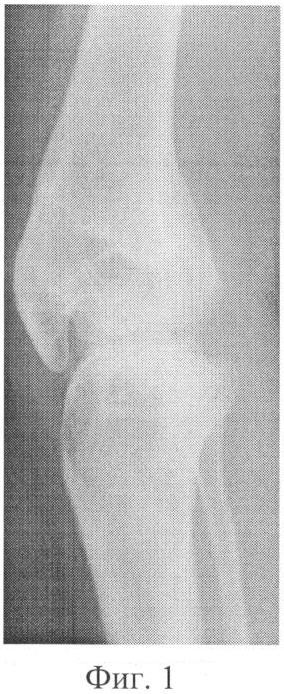

Способ поясняется описанием, примером практического использования и иллюстративным материалом, где на

фиг.1 – рентгенограмма коленного сустава больной до лечения;

Больная С. 23 г., МКСБ №16914, поступила на лечение в клинику РНЦ «ВТО» с диагнозом: последствия гематогенного остеомиелита; разгибательно-сгибательная контрактура коленного сустава, анкилоз феморо-пателлярного сустава.

При поступлении на лечение движения в коленном суставе 155-168°; надколенник неподвижен. Передача усилий четырехглавой мышцы на надколенник не определяется; движения в коленном суставе за счет собственной связки надколенника (фиг.1).